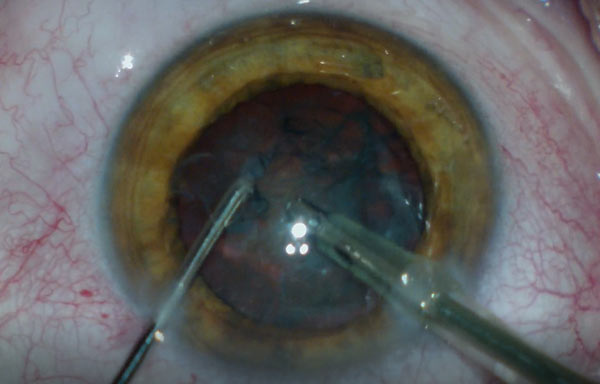

На сегодняшний день технология замены хрусталика стандартизирована и хорошо отработана. Потенциальные риски в общем случае несколько выше, чем при лазерной коррекции зрения, но в настоящее время такой тип операций выполняют даже на прозрачных хрусталиках с рефракционной целью (когда пациенту не нравится носить очки с толстыми стеклами), то есть это вполне «бытовая» задача для офтальмологии. Читать полностью »